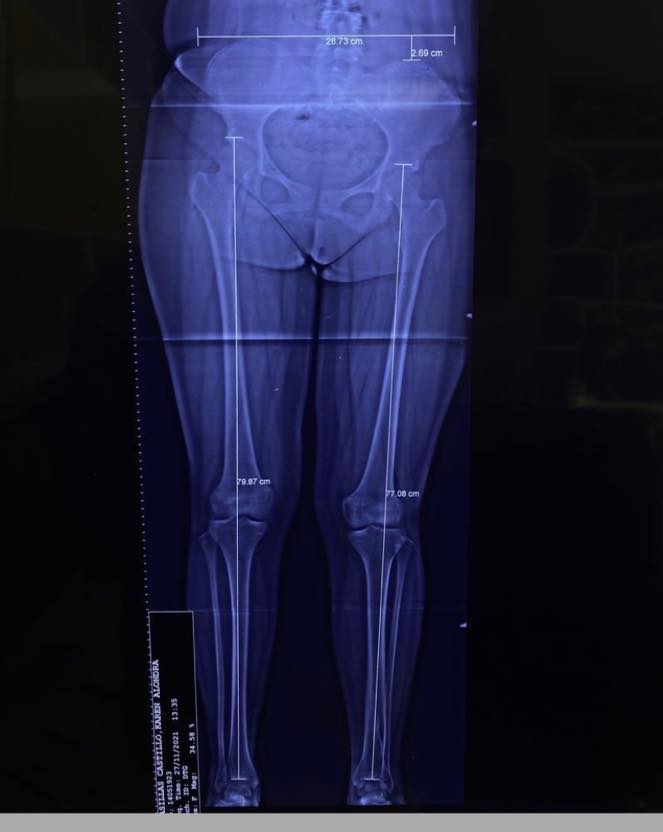

Hoy es un día especial y quiero aprovechar para compartir el caso de Emiliano, un joven de 17 años originario de Nayarit. Emiliano acudió conmigo por una deformidad en su pie, la cual había sido tratada quirúrgicamente en varias ocasiones sin éxito. Iniciamos un tratamiento con yesos, seguido de una cirugía para el balance neurológico del pie. Ahora, después de 5 meses, este es el resultado: Emiliano ya no necesita bastón para caminar y puede vivir libre y feliz.